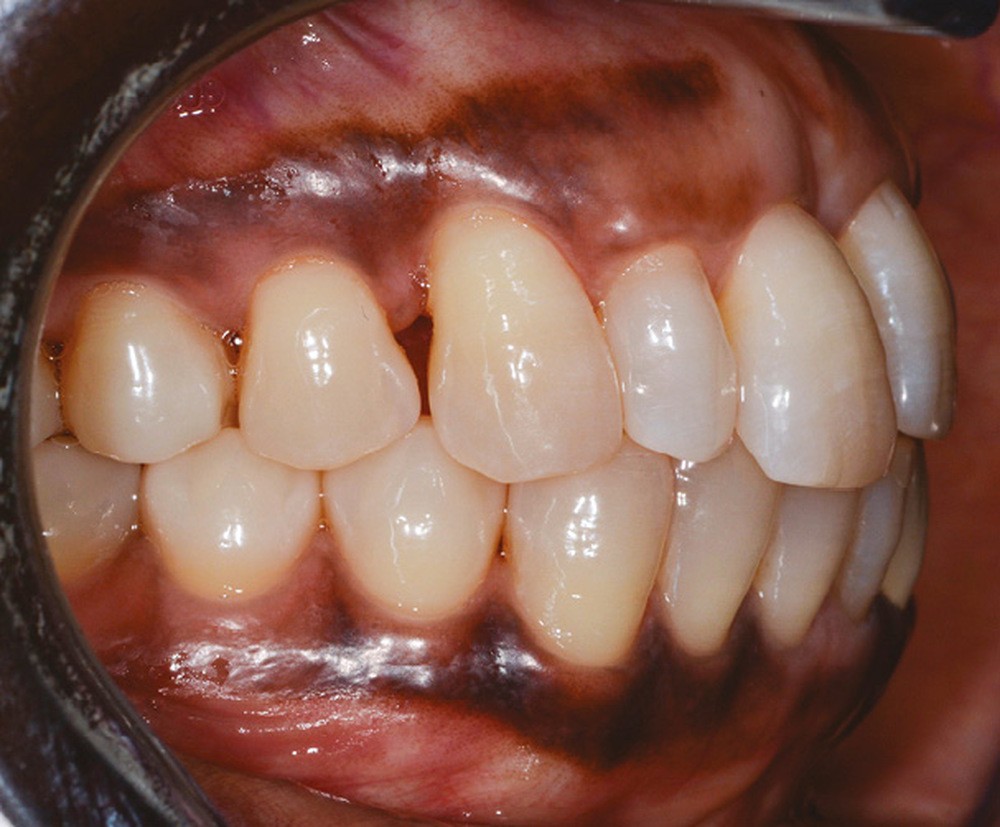

L’observation clinique après traitement parodontal initial révèle, au niveau interarcade, des rapports de classe I molaire bilatéraux associés à des rapports de bout à bout incisif. Dans la dimension verticale, elle présente une légère infraclusion antérieure. On ne note pas d’anomalie de la dimension transversale (fig. 3 à 5). À l’examen intra-arcade, on constate des diastèmes maxillaires interincisifs (1 mm), en distal de 13 (0,5 mm) et de 24 (1 mm) ainsi que des malpositions unitaires (linguoversion de 12, rotation mésio-vestibulaire disto-linguale de 24). À la mandibule, on observe une couronne céramométallique au niveau de 32 plus large de 1,5 mm que les autres incisives ainsi qu’une rotation mésio- linguale de 35 (fig. 6 à 8). En diduction, on note une interférence au niveau de 24.